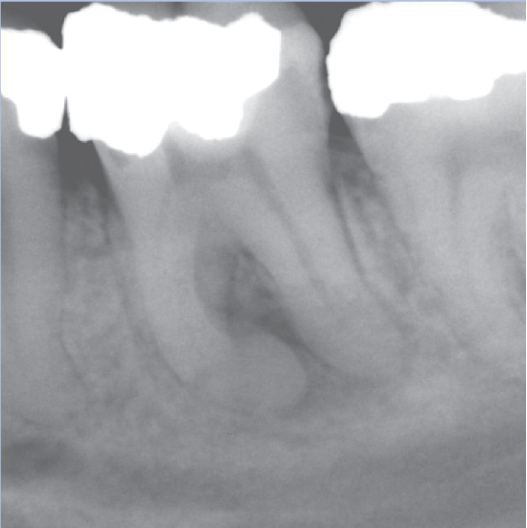

Before

After

Before Root Canal treatment

After Root Canal treatment